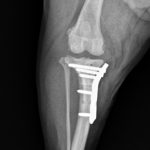

MIX犬(5.3kg)の右前十字靭帯断裂に対するTPLO術(脛骨高平部水平化骨切術)☑

雑種犬(22kg)の左前十字靭帯断裂に対するTPLO術(脛骨高平部水平化骨切術)☑

ビーグル(15kg)の左前十字靭帯断裂に対するTPLO術(脛骨高平部水平化骨切術)☑

ヨークシャーテリア(4.4kg)の左前十字靭帯断裂に対するTPLO術(脛骨高平部水平化骨切術)☑

ミニチュアシュナウザー(7.8kg)の右前十字靭帯断裂に対するTPLO術(脛骨高平部水平化骨切術)☑

トイプードル(4.3kg)の前十字靭帯断裂に対するTPLO術(脛骨高平部水平化骨切術)☑

ヨークシャーテリア(6.9kg)の前十字靭帯断裂に対するTPLO手術(脛骨高平部水平化術)☑

トイプードル(3.4kg)の前十字靭帯断裂に対するTPLO術(脛骨高平部水平化骨切術)☑

雑種犬(20kg)の前十字靭帯断裂に対するTPLO術(脛骨高平部水平化骨切術)☑

🦴 TPLOとは何か? TPLO(脛骨高平部水平化術)は、前十字靭帯が切れることで生じる膝関節の不安定性を、骨の角度を調整することで安定させる手術方法です。脛骨の上部を専用のソーで円弧状に切